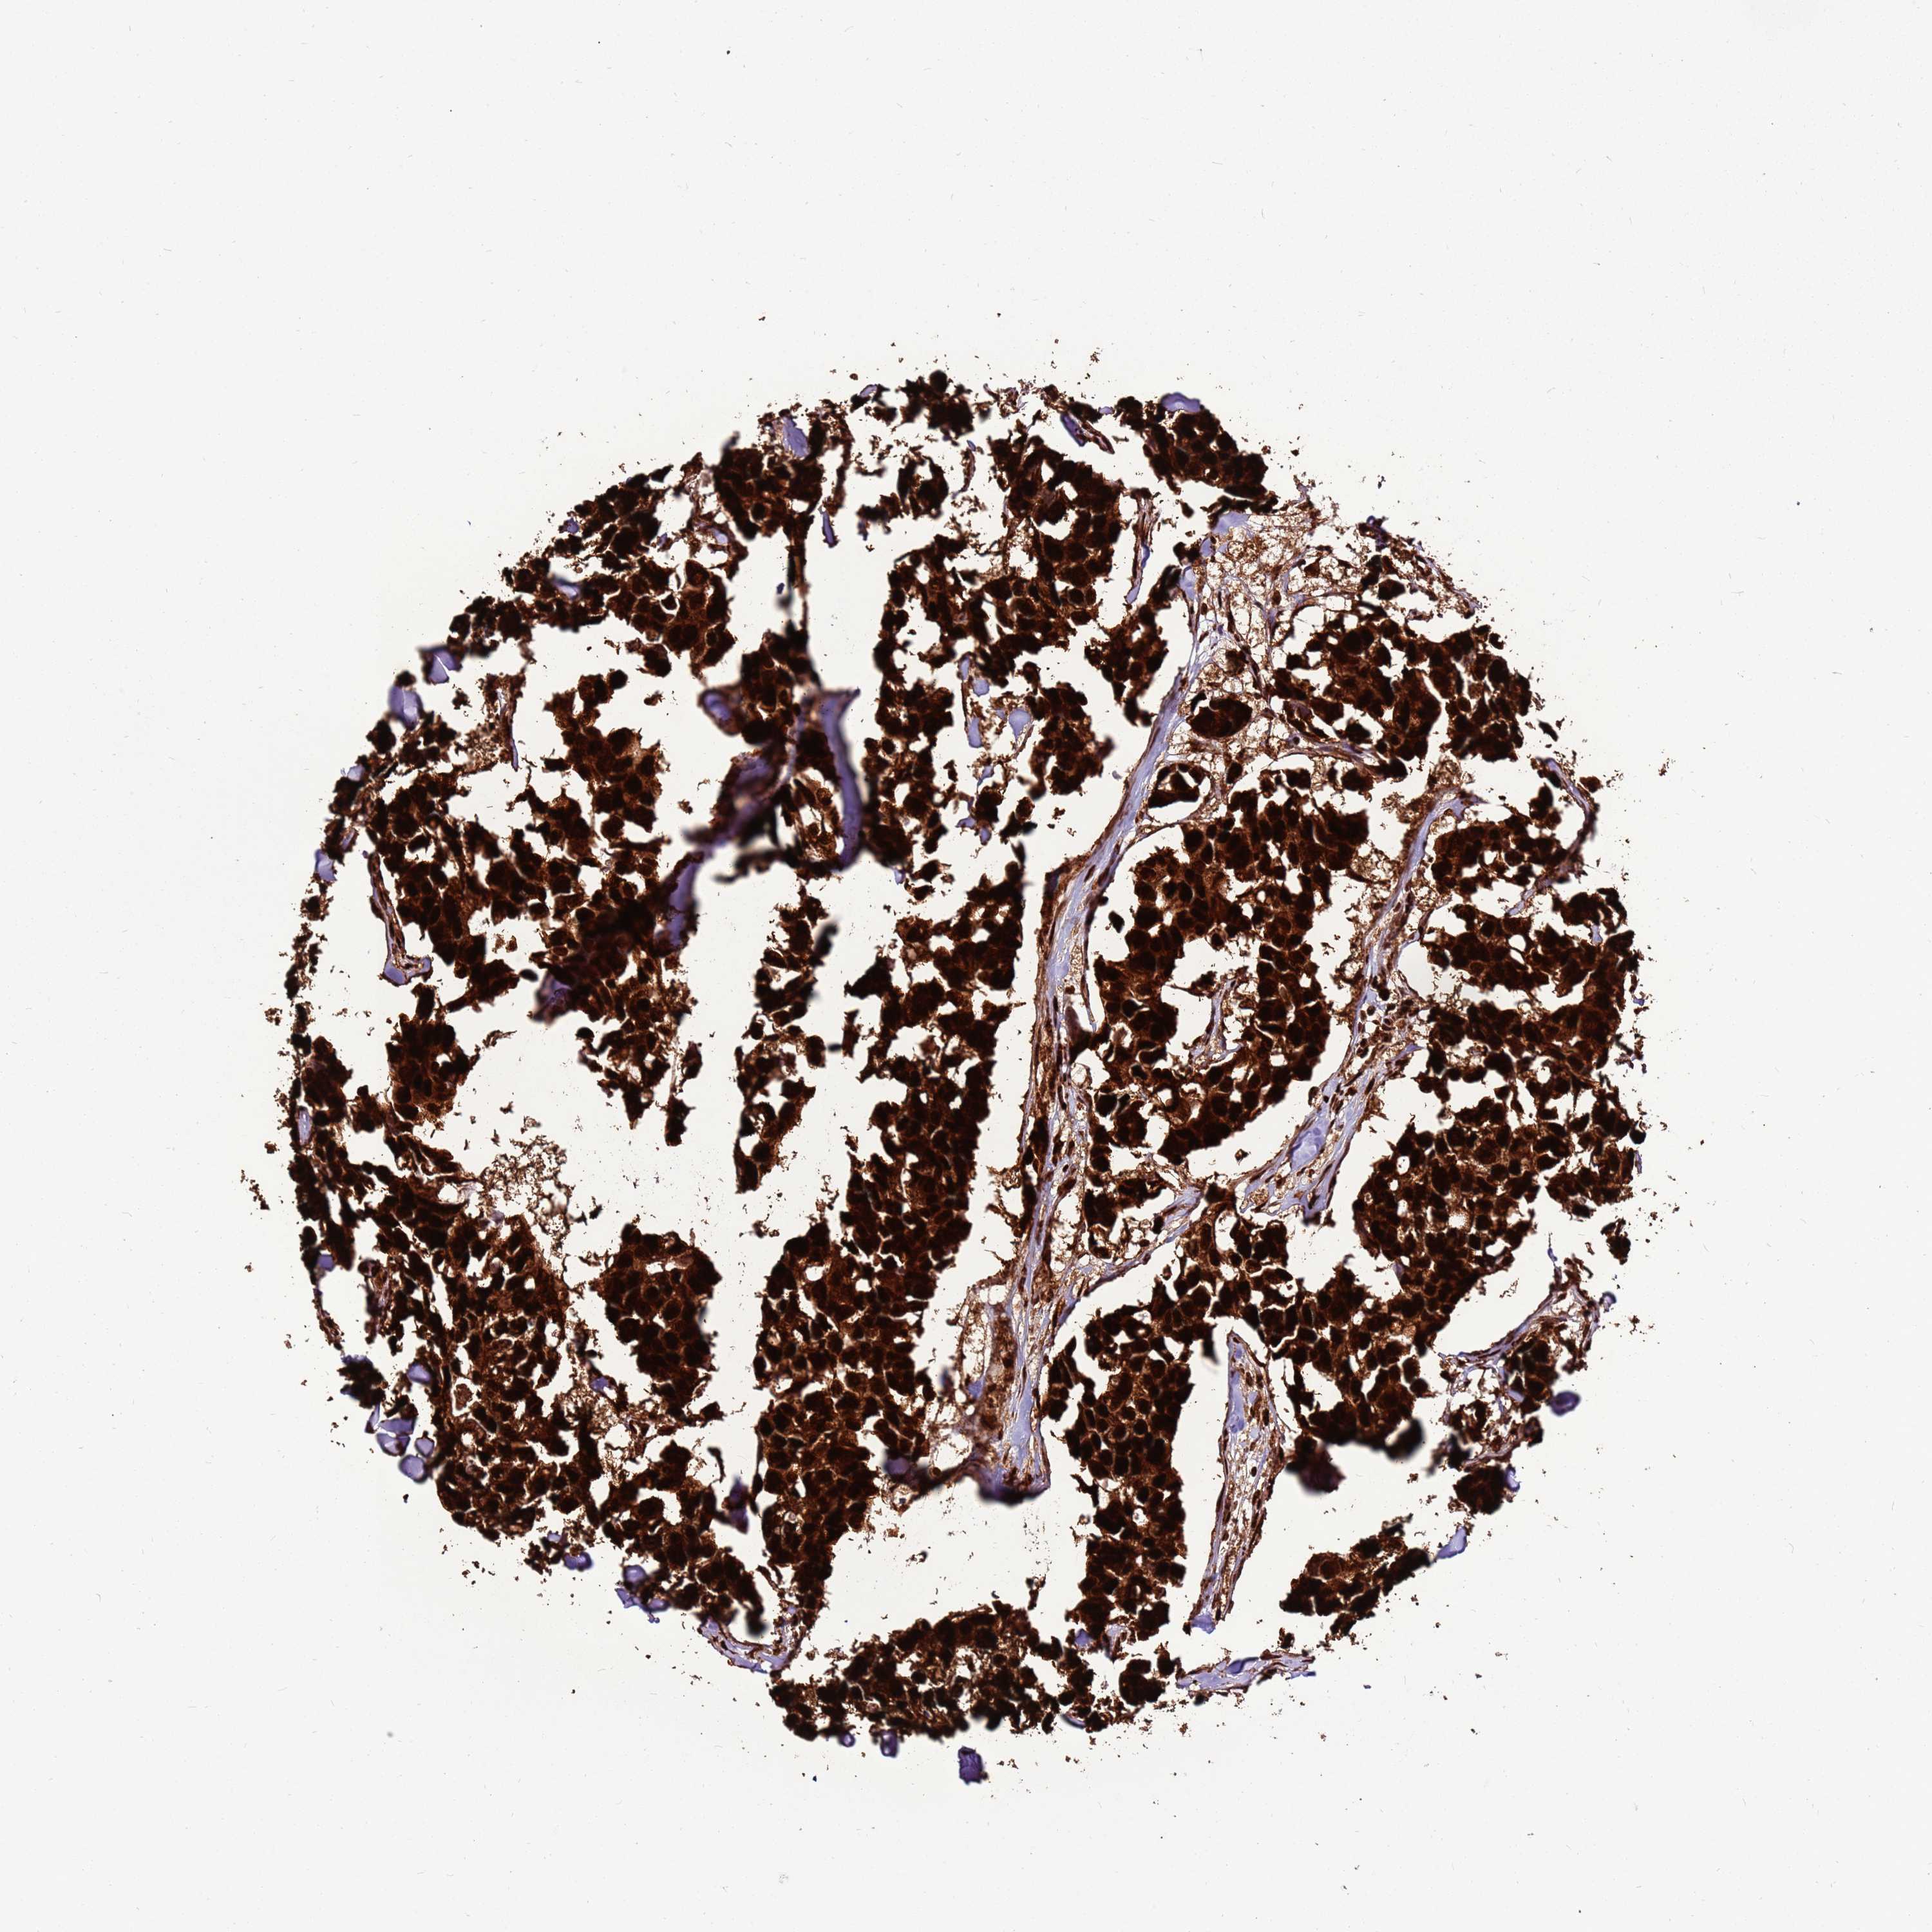

CANCER BREAST CANCER Show tissue menu

BRCA TCGA BRCA VALIDATION PROTEIN EXPRESSION

Breast cancer

Human cancer

Breast invasive carcinoma